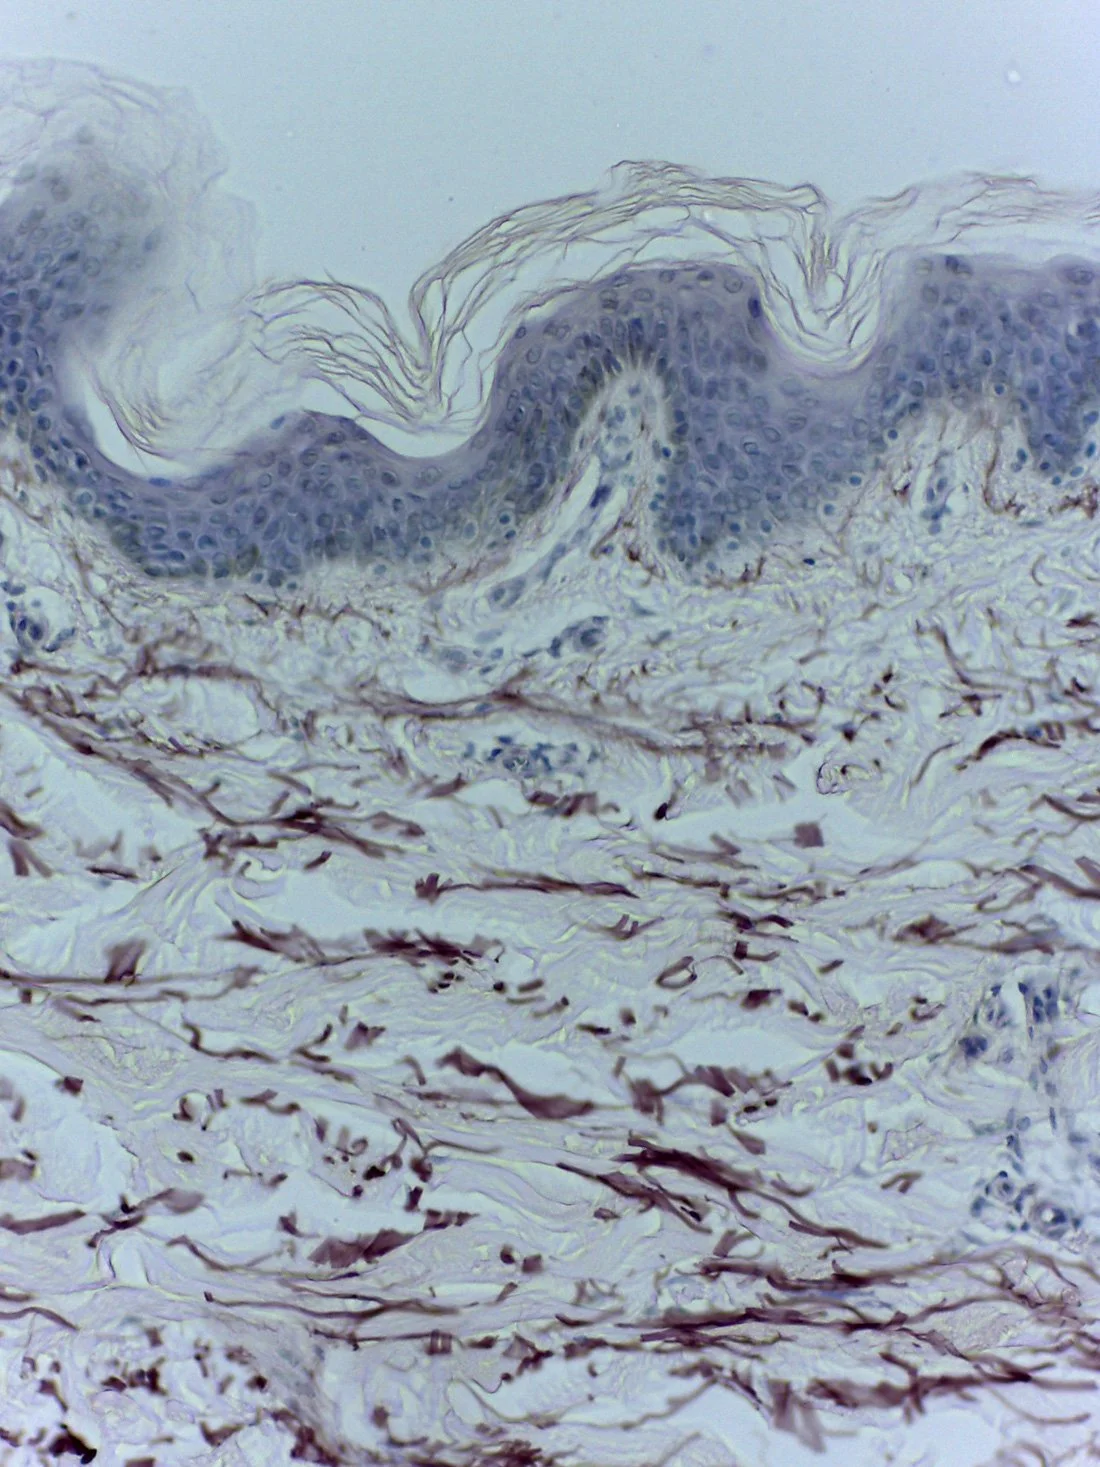

Young skin presents a thick epidermis with well-organized layers and high cellular proliferation in the basal layer, visible as a continuous line of cells with aligned nuclei, indicating good regenerative capacity. The dermis is rich in well-structured collagen with clearly defined bundles, ensuring firmness, while elastin fibers are fine and evenly distributed, providing elasticity. Overall, the skin shows a uniform, compact, and functional architecture.

Aged skin presents a thinner, more disorganized epidermis with reduced cellular proliferation, resulting in slower renewal and decreased regenerative capacity. The basal layer becomes irregular and less defined, with lower cell density. In the dermis, there is fiber disorganization, with fragmented elastin and altered collagen, leading to loss of firmness and elasticity, as well as the appearance of wrinkles and sagging.

Nas duas imagens seguintes, é fascinante observar a semelhança visual do tecido humano (à esquerda) com o tecido textile (à direita). Após esta experiência, considero ainda mais que a roupa é a nossa segunda pele. Com o tempo também esta se torna mais fina e mais degradada perdendo a sua flexibilidade. Interessa-me sobretudo elevar a beleza dessa fragilidade, de evidenciando as suas marcas em vez de as cobrir, corrigir ou apagar.

In the following two images, it is fascinating to observe the visual similarity between human tissue (on the left) and textile fabric (on the right). After this experience, I am even more convinced that clothing is our second skin. Over time, it too becomes thinner and more worn, losing its flexibility. I am particularly interested in highlighting the beauty of this fragility, by revealing its marks rather than covering, correcting, or erasing them.